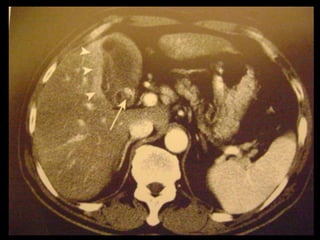

Achados na TC: cálculos biliares, espessamento da

parede, alterações inflamatórias

perivesiculares, bile com alta

atenuação, borramento da interface VB-fígado e

aumento transitório da atenuação do fígado

perivesicular;

Colecistite aguda US é a modalidade de imagem de escolha; Em geral, a TC é realizada para avaliar pacientes com suspeita de complicações do quadro de colecistite aguda, como perfuração por exemplo. Achados na TC: cálculos biliares, espessamento da parede, alterações inflamatórias perivesiculares, bile com alta atenuação, borramento da interface VB-fígado e aumento transitório da atenuação do fígado perivesicular;